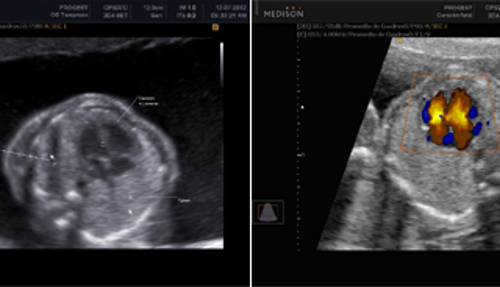

Se realiza por vía abdominal después de la semana 13 y hasta el final de la gestación. Esta ecografía brinda información muy útil sobre la anatomía del bebe, donde se evalúa cada uno de sus órganos, y es de gran utilidad para descartar problemas estructurales o de funcionamiento de algún órgano , formación y crecimiento del bebe, posición de la placenta, cantidad de líquido amniótico, tiempo de gestación, como está la circulación de la placenta y el cordón umbilical, entre otras. A partir de la semana 16 podemos determinar el sexo de tu bebé con una ecografía tradicional en 2D